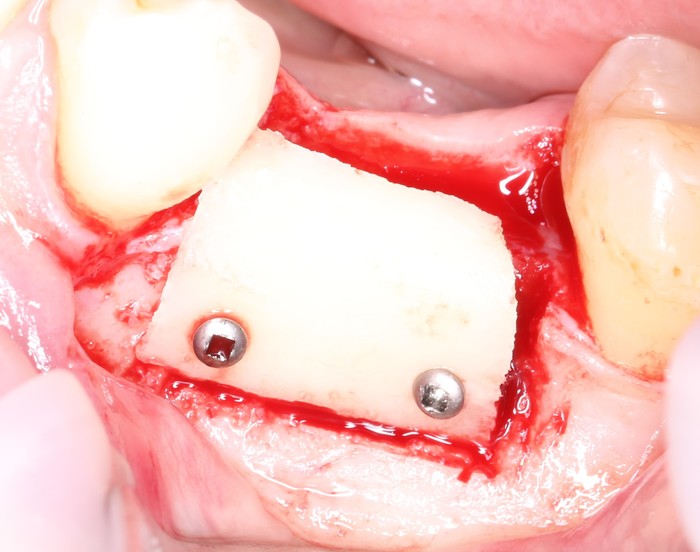

На верхней челюсти было дополнительно удалено два боковых резца с одномоментной установкой имплантатов, так же они были установлены в области четверок и шестых зубов. Дополнительно было проведено наращивание костной ткани - двусторонний синус - лифтинг. О том, что это такое, можно почитать ТУТ и ТУТ.